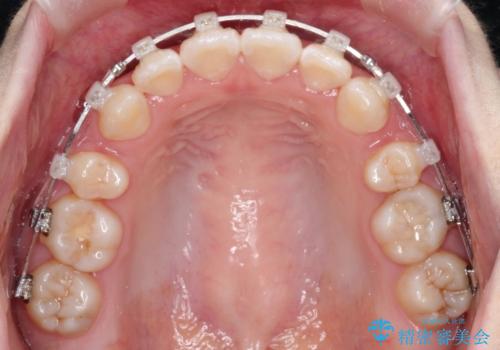

- 矯正装置

- 審美装置

- ”口元を下げたい”が主訴で来院されました。

抜歯してワイヤー矯正を行い、口元も改善され大変満足していただきました。

小臼歯の抜歯を行うことで口元を改善することができました。